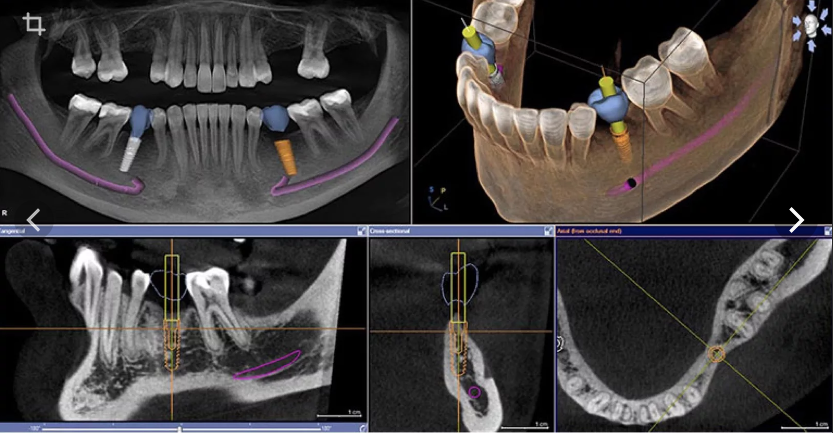

Этот курс был разработан специально для стоматологов, которые хотят уверенно работать с цифровыми технологиями. За 3 вебинара вы пройдёте путь от основ навигации и моделирования шаблонов до планирования тотальных реабилитаций и разбора хирургического протокола с клиническими примерами.